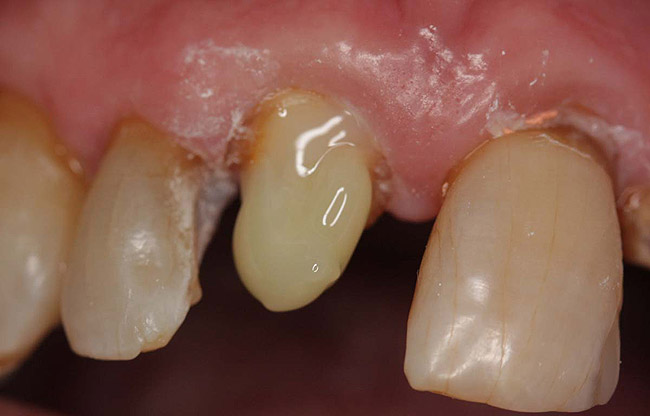

Case 1

A Class IN maxillary bicuspid was previously restored with a fiber post and an all-porcelain crown (Figure 1). The forces of the oral environment resulted in fracture of the fiber post and crown failure. The remaining fiber post in the root was removed, and anti-rotational areas were prepared for a cast post (Figure 2). A gold cast post was constructed at a dental laboratory, using an indirect technique (Figure 3). A porcelain-fused-to-metal (PFM) crown was constructed with a bevel finish to provide a ferrule and reduce forces on the post (Figure 4 and Figure 5).

Figure 5  The final crown.

Figure 5